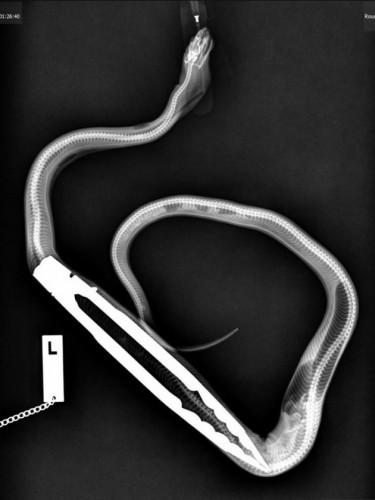

Специалистами университета Аделаиды, расположенного на Австралийском континенте, был спасен питон, который случайно проглотил щипцы для барбекю. У Аарона Роуза есть домашний питон, которого владелец назвал Уинстоном. Аарон решил накормить своего любимца крысой, которую придерживал щипчиками для барбекю. Он не ожидал, что питон вцепится в щипцы мертвой хваткой и не отпустит их. Роуз отошел на некоторое время, а по возвращении к своему питомцу увидел, что щипцы бесследно исчезли. Оказалось, что питон проглотил их вместе с крысой. Хозяину пришлось срочно везти питона в университет Аделаиды, который славился находящимся на его территории Центром по спасению домашних животных.

Оливер Фунел, университетский ветеринар, рассказал о том, что сразу не мог поверить, что небольшому питону удалось целиком проглотить щипцы. Однако, взглянув на змею, он все понял, поскольку Уинстон принял форму проглоченного предмета. Хотя змеям отлично удается отрыгивать проглоченные предметы, питон не спешил это сделать. Может быть, из-за острых краев щипцов, раздражающих его пищевод, мышцы Уинстона не могли сокращаться так, как необходимо для отрыгивания.

Вначале группа докторов хотела достать щипцы, используя эндоскопию, но затем они побоялись нанести питону внутренние повреждения, поэтому извлекли их хирургическим вмешательством. К счастью, операция оказалась успешной, поэтому самочувствие Уинстона отличное. Врачи взяли с владельца питона обещание, что тот будет более внимателен к своему любимому питомцу.